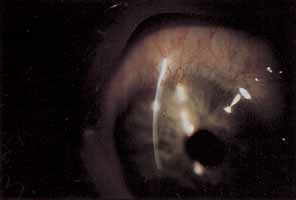

STERILE INFILTRATES

Sterile corneal infiltrates associated with contact lens wear are generally multiple, small, anterior stromal infiltrates found most often at the corneal limbus but also in clusters in the central cornea (Fig. 4).130–132 Rarely the epithelium alone may be involved and is commonly intact over stromal infiltrates. The anterior chamber may show mild to severe cellular reaction.130 Corneal infiltrates related to extended soft lens wear tend to form near the superior limbus.133 These infiltrates must be distinguished from their infectious counterparts, including chlamydia, by careful historical consideration and clinical examination.131 If there is any doubt regarding the etiology of the infiltrates, scrapings for stain and culture should be taken, followed by appropriate broad-spectrum topical antibiotic therapy.

Fig. 4 Twelve o'clock sterile marginal corneal infiltrate.

Using rigid gas permeable lens wear as the referent, soft lens wearers and particularly extended soft lens wearers carry a significantly higher risk of developing sterile infiltrates.6,9,130,134 PMMA lens wearers are the least likely to suffer this complication.134 A longer duration of soft lens wear provides a proportionately increased risk of developing these infiltrates.132,135 The rate of sterile infiltrates per year for disposable extended soft lens wear in a prospective study was as high as 7%, suggesting that disposable lenses are not the solution to this problem.136 Daily disposable soft lenses or soft silicone hydrogel lenses afford the lowest rate of peripheral infiltrates for soft lens wear.22,132

Various theoretic causes include chemical hypersensitivities to thimerosal and chlorhexidine, exposure to a variety of environmental toxins through digital contamination, improper enzyme use, staphylococcal lid disease, and bacterial contaminants of contact lens cases.130,137 Antigenic debris held chronically against the corneal surface has been cited as a potential basis for sterile infiltrates, particularly with extended soft lens wear.130–134

Required therapy consists of discontinuing lens wear and treating cautiously with topical corticosteroids, a practice that necessitates frequent initial examinations.130 Lens wear should cease until there is complete resolution of all infiltrates and adequate corticosteroid taper. Recurrences may be avoided by careful review of contact lens care and handling, cessation of suspected offending chemicals, insistence on clean contact lens cases and treatment of any associated staphylococcal lid disease. Recurrent infiltrates associated with extended soft lens wear may require the use of soft or rigid daily wear lenses. Daily disposable and silicone hydrogel soft lenses are an excellent strategy for prevention in susceptible individuals. The prognosis for the majority is good, with visual loss remaining rare.